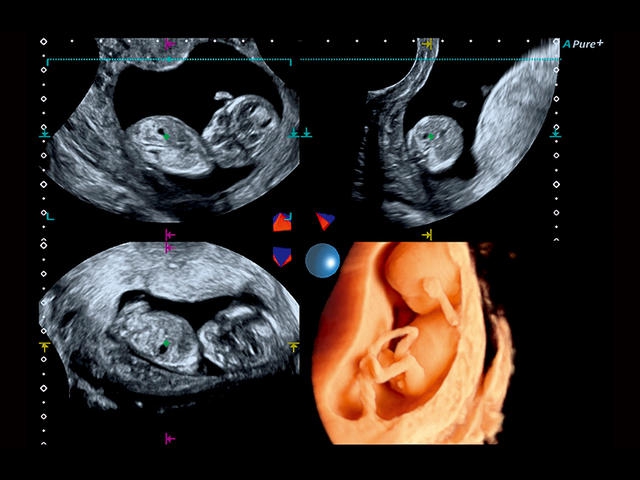

Aplio 500 – ультразвуковой сканер премиум класса, сочетающий в себе быстродействие диагностики и отличное качество визуализации. Более 30 датчиков на выбор, в т.ч. матричные, монокристаллические, 4D, эндоскопические для любых типов исследований. Ультразвуковой сканер позволяет изучать анатомические структуры в высоком разрешении.

Обновленная версия легендарного УЗ-сканера. Стационарный аппарат экспертного класса Aplio 500 Toshiba NEW, визуализирует анатомические структуры в высоком разрешении. Модель позволяет выявить микрокальцификаты, новообразования, нарушения в работе сердца, сосудов и мышц. Присутствует функция виртуальной эндоскопии, 4D-сканирования, эластометрии тканей, УЗИ с контрастированием. За повышение качества изображения отвечают технологии ApliPure и Superb Microvascular Imaging. Первая задействует возможности пространственного и частотного кодирования, формирует цельный визуальный ряд с сохранением клинических маркеров. Вторая улучшает отображение микрососудистого русла, используя доплеровский эффект. Модель оснащена 21-дюймовым монитором, имеет 4 активных порта. Возможно подключение педиатрических, интраоперационных, лапароскопических и чреспищеводных датчиков.

• Fly Thru. Виртуальная эндосонография обеспечивает построение трехмерной модели полостей, протоков и сосудов в рельном времени, облегчает организацию инвазивных процедур и динамических исследований. Посредством Fly Thru можно установить шунты и стенты, проводить точные оперативные вмешательства.